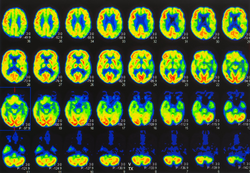

Aging neuroscience explores how the brain changes over time and what drives cognitive decline, resilience, and neurodegeneration. Our Research Topics examine the biological, psychological, and environmental factors shaping brain aging, from molecular mechanisms to clinical interventions. By advancing understanding across disciplines, we aim to support healthier aging and improve brain health worldwide.